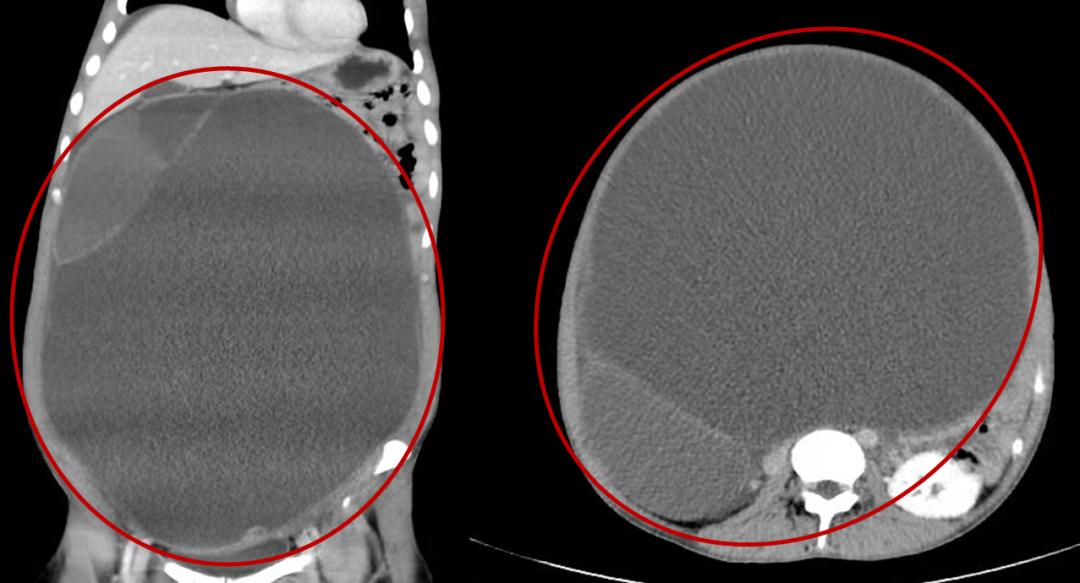

再进一步做CT等相关检查后

医生表情凝重:

“这真不是胎儿!

而是一个超大盆腹腔肿物!”

(▲红色圈内为小兰盆腹腔里的巨大肿物)

一个直径超30厘米的

超大盆腹腔肿物

占满了小兰的整个腹腔和盆腔

把她肚子都快撑破了